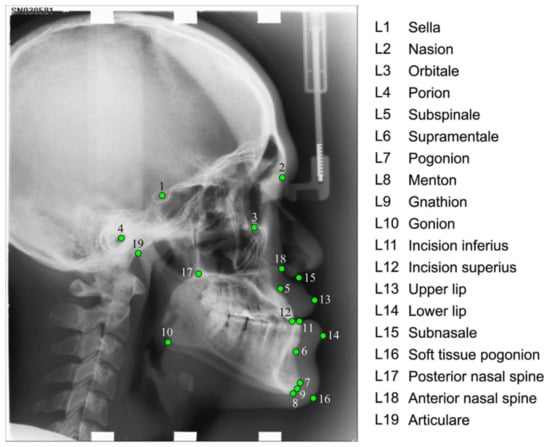

- Fully Automatic System for Accurate Localisation and Analysis of Cephalometric Landmarks in Lateral Cephalograms—Scientific Figure on ResearchGate. Available online: https://www.researchgate.net/figure/Cephalogram-annotation-example-showing-the-19-landmark-positions-used-in-this-study-A_fig1_308384067 (accessed on 5 June 2023).